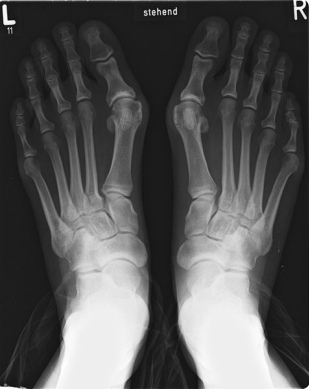

Die Fussverstümmelung eines Spreizfuss mit Schiefzehe (Hallux valgus), hier an einem Röntgenfoto sichtbar [web9] [Foto 28]